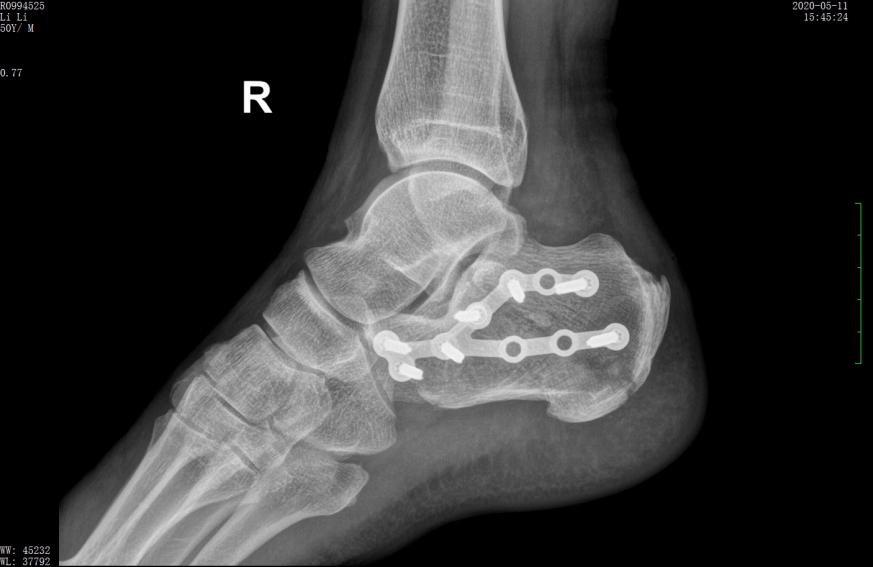

案例2影像

术后X线示骨折复位良好